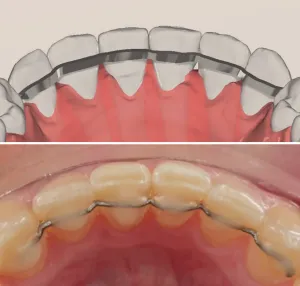

Retainer in Beta Titanio Biomedicale

Dispositivo di contenzione post-trattamento progettato per mantenere i risultati ottenuti. Garantisce stabilità a lungo termine.